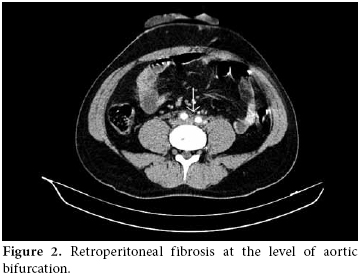

A 28-year-old male patient was admitted to our hospital with complaints of severe abdominal pain and nausea which had started six weeks previously. There were painful, maculopapular lesions that responded well to a topical steroid in both of the palms. The patient had also been suffering from photosensitivity for the last eight months. He had been diagnosed with type 1 diabetes mellitus (DM) and prothrombin 20210a gene mutation during the last 12 years and he had also a history of deep vein thrombosis (DVT) in 2002 and pulmonary thrombo embolism (PTE) in 2006. His mother also had a history of prothrombin 20210a gene mutation and type I DM. He was being treated with a daily dose of glargine insulin and warfarin. His physical examination at the time of admission revealed hypertension (170/100 mmHg), maculopapular lesions on both palms, hepatosplenomegaly, and abdominal tenderness. The laboratory examination was as follows: white blood cells (WBC) counts 15000/mm3, hemoglobin 16.3 gr/dl, platelets 92 000/mm3, blood urea nitrogen (BUN) 20 mg/dl, creatinine 1.46 mg/dl, erythrocyte sedimentation rate (ESR) 40 mm/h, C-reactive protein (CRP) 8.8 mg/dl (0-0.8), and fibrinogen 712 mg/dl (219-403). A urinalysis presented the following results: +++protein, +++blood, no casts, and microprotein in 24 h urine 900 mg/day (0-80). The serologic tests were the followiong: anti-nuclear antibodies 1/320 (homogeneous pattern), anti-double-stranded deoxyribonucleic acid (anti‐dsDNA) 1.7 (0-1.1), rheumatoid factor 22.0 IU/mL (0-15), anti-cardiolipin IgG>300 GPL/mL (0-15), and anti-phospholipid IgG 232 GPL/mL (0-15). A chest X-ray showed minimal pleural effusion and the electrocardiography ECG was normal. There was no thrombus and no vegetation in the transesophageal echocardiography (TEEC). For further evaluation of the thrombocytopenia, bone marrow aspiration and a biopsy were performed, but there were no pathological findings to explain the situation. Also, a skin biopsy from the palms was done to search for the etiology, but this also yielded no clues. Angiography with abdominal computed tomography revealed a thickening of the wall of the thoracic and abdominal aorta and an increased density of the surrounding fat tissues at the level of bifurcation. These were compatible with the diagnosis of vasculitis and retroperitoneal fibrosis (figures 1 and 2).